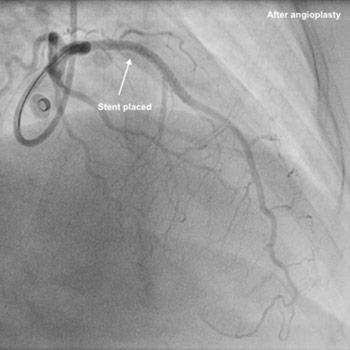

Triple vessel angioplasty (stenting) via radial approach (wrist).

This lady was seen in clinic with history of chest pain and found to have Treadmill test (TMT) +ve in Aug 2015. She was reviewed by our team and advised coronary angiography, but she didn’t turn up. After 2 months she came to see me again in OPD. In between, she had undergone angiogram in another hospital in the city, as someone known to her recommended that. After the angiogram, she was advised that she has block in 2 arteries and advised 2-vessel angioplasty. The family took the report and the CD to one another hospital in the city. They were told there were blockages in all 3 arteries and advised either angioplasty or bypass surgery (CABG). She and the family got confused with this and decided to come and see me. I reviewed the angiogram and explained to them about the problem- all 3 vessels had blockages, but all blockages are focal- which essentially means no need for long stents. After informed consent, we performed 3-vessel angioplasty through the wrist and inserted 3 stents successfully. She was discharged home in 2 days and been under my follow up since then. It is now more than 4 years and she is doing remarkably well with regular exercise and no symptoms. She has also travelled to Saudi Arabia to see her son for few months and been back.